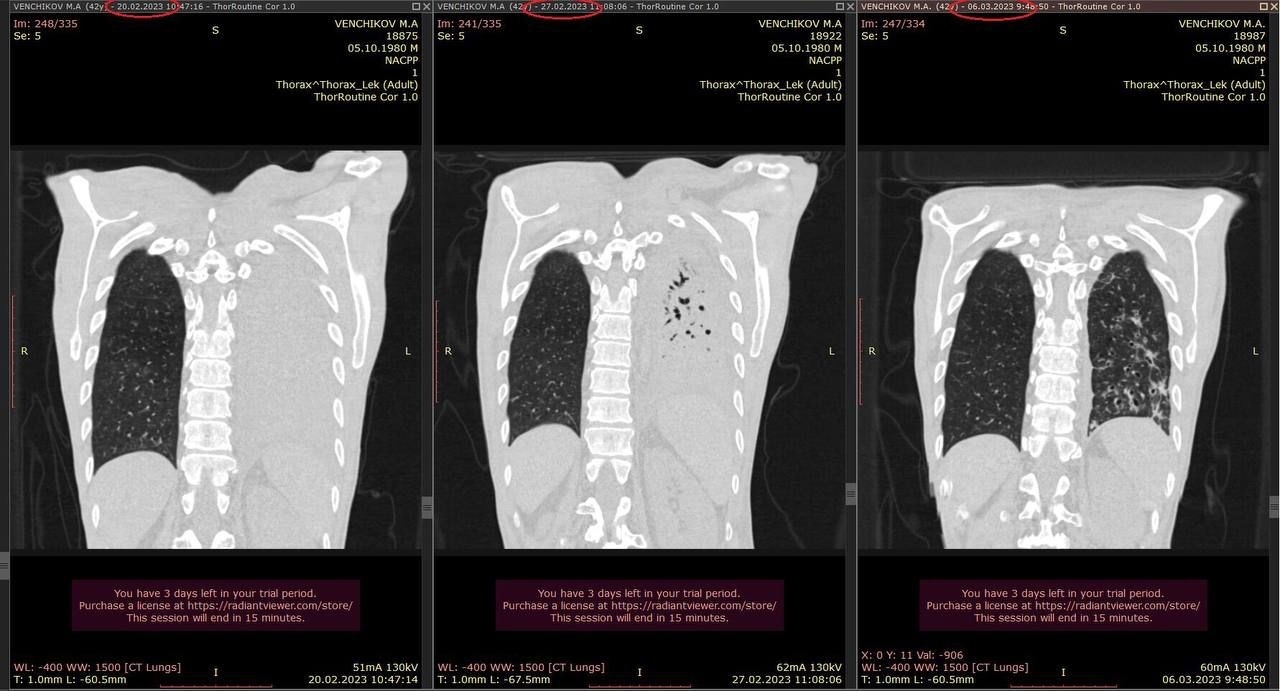

Знакомьтесь, это Макс! Ему 42 года. У него рак пищевода. С 2022 года он получал химиотерапию, но потом она перестала работать и опухоль проросла в левый бронх и его левое легкое перестало работать (тотальный ателектаз). Далее присоединилась пневмония и ему из-за этого отказали в лечении. Никто не хотел рисковать.

У нас после двухнедельного курса антибиотиков, доктора (на фото онколог и терапевт) уговорили меня рискнуть и провести новый курс химиотерапии. Риски: сепсис и т.д. Спустя 5 дней после химии на контрольном снимке опухоль в бронхе ушла и левое легкое снова расправилось и задышало. Сегодня мы его выписали домой.

Если химия будет так же работать, то мы постараемся его вывести на операцию.